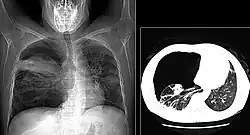

El diagnóstico de neumonía por Pneumocystis se realiza mediante la identificación del organismo a partir de una muestra de expectoración, líquido de los pulmones afectados o una toma de biopsia pulmonar. [4] [3] Una radiografía y una tomografía de tórax de los pulmones afectados muestra una sombra generalizada en ambos pulmones, con un patrón de "ala de murciélago" y una apariencia de vidrio esmerilado o deslustrado. [2] [7] Se pueden usar tinciones de Giemsa o de plata para identificar el organismo, así como la inmunofluorescencia directa de las células infectadas. [3]